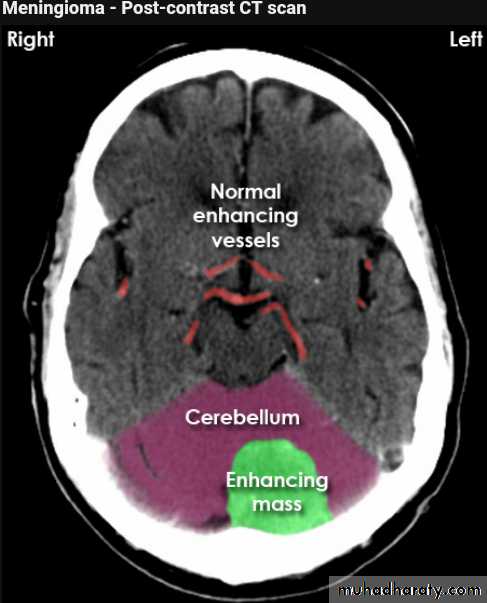

CT finding

meningioma presented as isodense area or slightly hyper density area with surrounded crescent of hypo density ( csf cap ) post contrast injection the lesion enhance homogeneously with enhancing Dural tail .

20 % show calcification

hyperostosis & thickening of the near by bony part of the skull & diplioc space .

it may be associated with little or no peri focal edema .